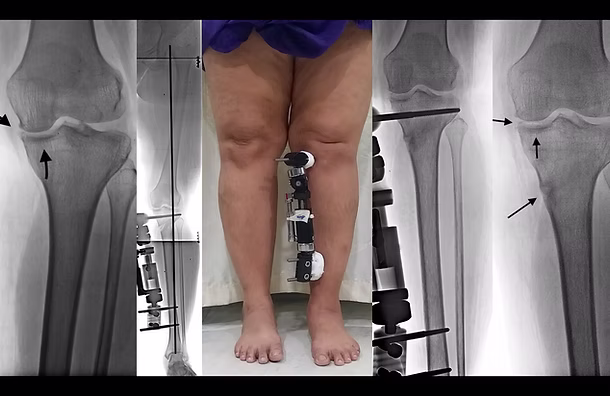

The Ilizarov technique is a specialized orthopedic method used to correct bone deformities, treat nonunion fractures, and perform limb lengthening using an external circular fixator.

Yes, both conditions can be successfully corrected in adults using advanced techniques such as osteotomy and the Ilizarov fixator.